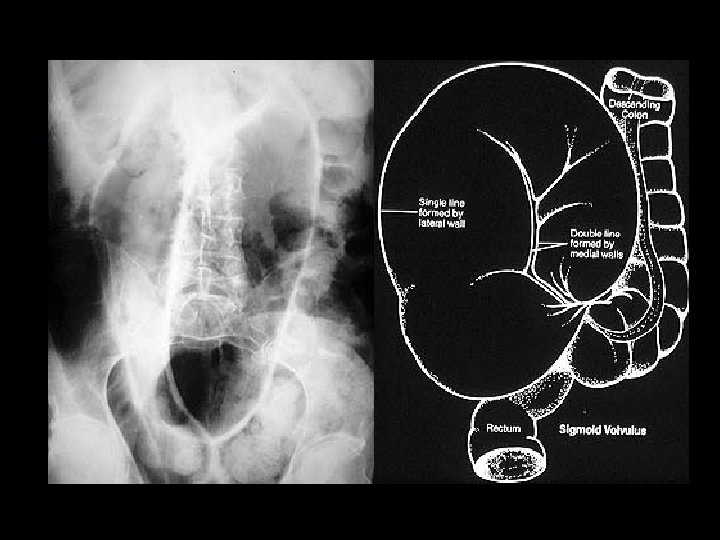

Karın Muayenesinde Patolojik Bulgular-2 • Perküsyon: Kc matitesinin yerini timpanikses=ülser perforasyonu, kutanöz hiperestezi, sağ üst kadranda ağrı=kolesisit, distandü karında yaygın timpanizm=sigmoid volvulus, obstrüksiyon…. • Palpasyon: Ağrı, hassasiyet, rebound, defans, rijidite, rovsing, HM, SM, asit varlığı, kitle (abse, tm vs. )Murphy bulgusu, Courvoisier bulgusu…